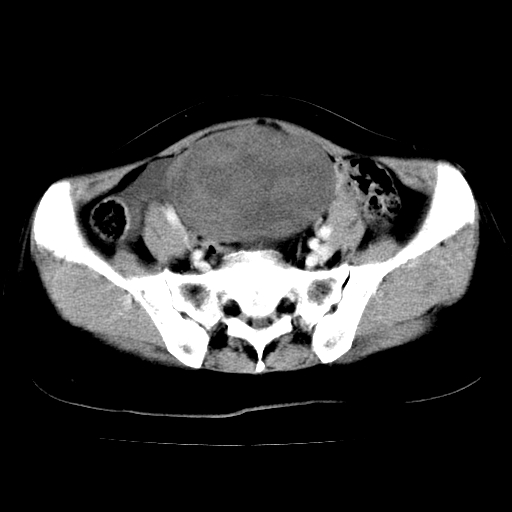

标题: CT24785:女,62岁,发现下腹部肿物半年。 [打印本页]

标题: CT24785:女,62岁,发现下腹部肿物半年。

女,62岁,发现下腹部肿物半年,下腹部不适。

老年女性患者,盆腔囊实性占位,ct增强不均匀强化,未见壁结节,未见腹水及盆腔积液,考虑附件囊腺瘤可能性大!